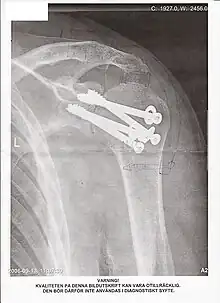

Une arthrodèse est une intervention chirurgicale destinée à bloquer une articulation lésée par l'obtention d'une fusion osseuse (en général de l'extrémité des os) dans le but de corriger une déformation ou d'obtenir l'indolence. C'est souvent une opération non réversible. L'opération inverse, qui consiste à désolidariser des os fusionnés, s'appelle une désarthrodèse.